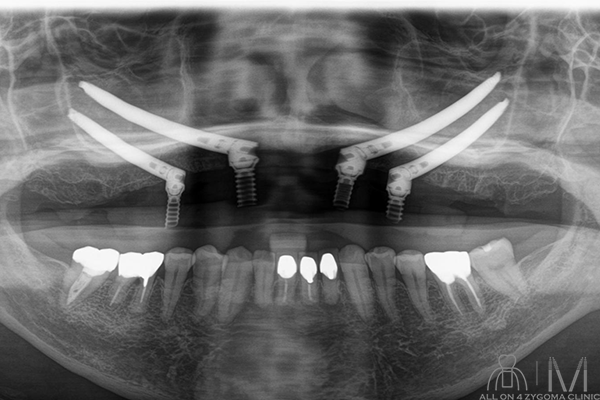

術後パノラマ画像所見

上顎に4本ザイゴマインプラントと4本のアバットメントにテンポラリーシリンダーが装着されているのを認める。左右の上顎洞に明らかな曇りは認めない。